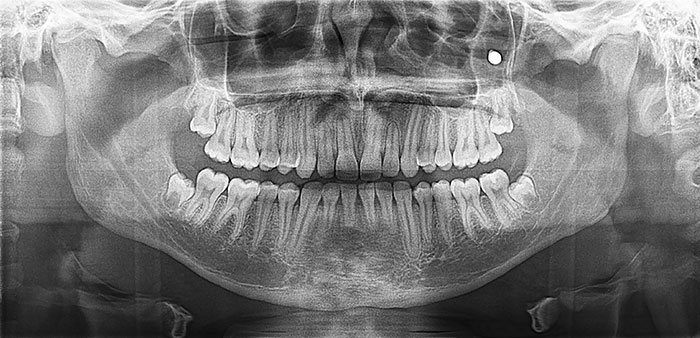

I Have A Rare Disorder Called Cleidocranial Dysotosis. Got My First Dental X-Ray Today And I Have A Lot Of Extra Teeth

I Got A Panoramic X-Ray Of My Teeth The Other Day. The Dentist Forgot To Have Me Remove My Glasses